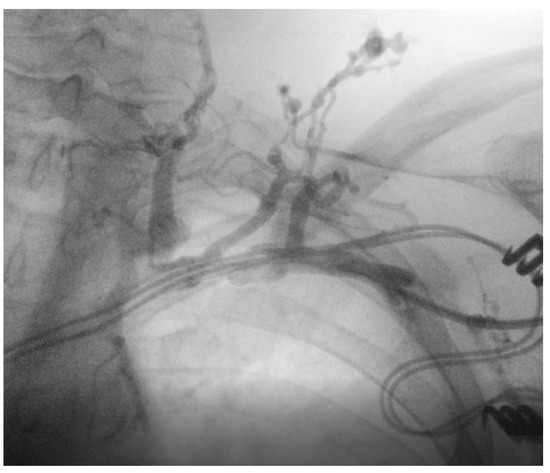

At the time of admission to our department, the patient was asymptomatic. The ECG showed a sinus rhythm with biventricular paced activity triggered by the atrial activity. An echocardiogram revealed normal left ventricle function with preserved ejection fraction, mild tricuspid regurgitation, and no visible vegetations. A chest X-ray revealed a normal cardiothoracic ratio, a pulse generator PM placed subcutaneously in the left subclavian area, and three leads (as shown in Figure 8).

Figure 8. Chest X-ray at the time of admission at the hospital, with one lead positioned in the right atrial appendage, one on the apex of the right ventricle, and another one in the posterolateral vein.